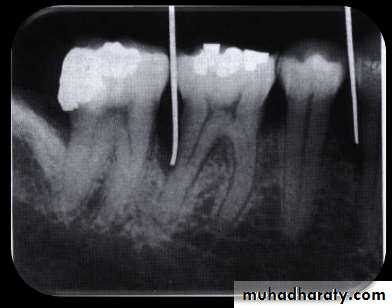

• The only accurate method of detecting and measuring periodontal pockets is careful exploration with a periodontal probe• Pockets are not detected by radiographic examination.

• The periodontal pocket is a soft tissue change

• Radiographs indicate areas of bone loss where pockets may be suspected but :

• they do not show pocket presence or depth

• They show no difference before or after pocket elimination unless bone has been modified

• Guttapercha points or calibrated silver points 19 can

• be used with the radiograph to assist in determining the level of attachment of periodontal pockets

• Blunted silver points assist in locating the base of pockets

• Radiographic findings are sometimes helpful in differentiating between a periodontal and a periapical lesion

• Early acute periodontal and periapical abscesses present no radiographic changes.

• Ordinarily, a radiolucent area along the lateral surface of the root suggests the presence of a periodontal abscess, whereas apical rarefaction suggests a periapical abscess.